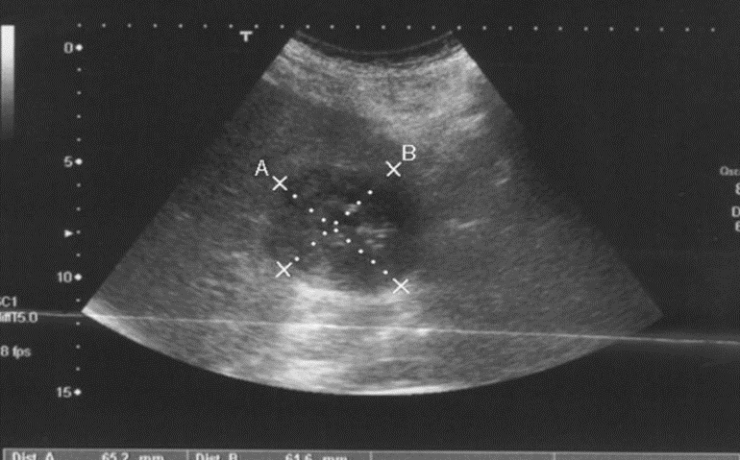

Hemangioma hepático poliquístico simulando un quiste hidatídico

El hemangioma cavernoso se define como una malformación vascular congénita y es considerado el tumor hepático benigno más frecuente. Tiene una prevalencia del 1 al 2%, afectando principalmente al sexo femenino a razón de 2:1 ò 5:1 variablemente. Habitualmente son asintomáticos y se detectan como